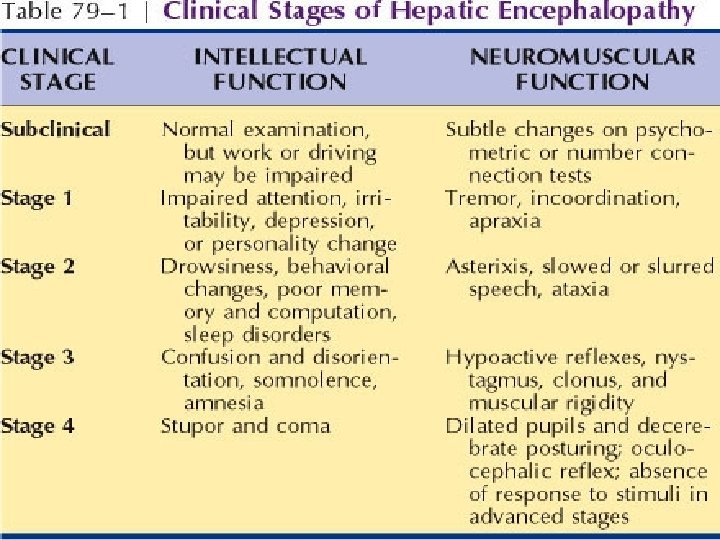

Hepatic Encephalopathy Reversible impairment of neurological function secondary to liver disease Acute: seen with acute liver failure Acute on chronic: in established cirrhosis

Clinical features Chronically, there is a disorder of personality, mood and intellect, with reversal of sleep rhythm. The patient is irritable, confused, disoriented and has slow slurred speech. Coma occurs as the encephalopathy becomes more marked, but there is hyperreflexia and increased tone.

Signs include: Fetor hepaticus Flapping tremor (asterixis) Constructional apraxia (the patient is unable to draw a five-pointed star) The ability to join numbers and letters with a pen within a certain time is prolonged